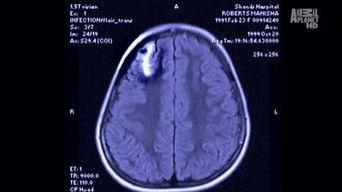

Suicide Attackers